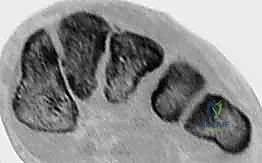

4. التصوير بالرنين المغناطيسي (MRI)

يُستخدم التصوير بالرنين المغناطيسي لتقييم الحالات التي يُشتبه فيها بوجود إصابة رباطية بحتة (تمزق في رباط ليزفرانك دون وجود كسور عظمية). الـ MRI قادر على إظهار الأنسجة الرخوة بوضوح وتأكيد التمزق.